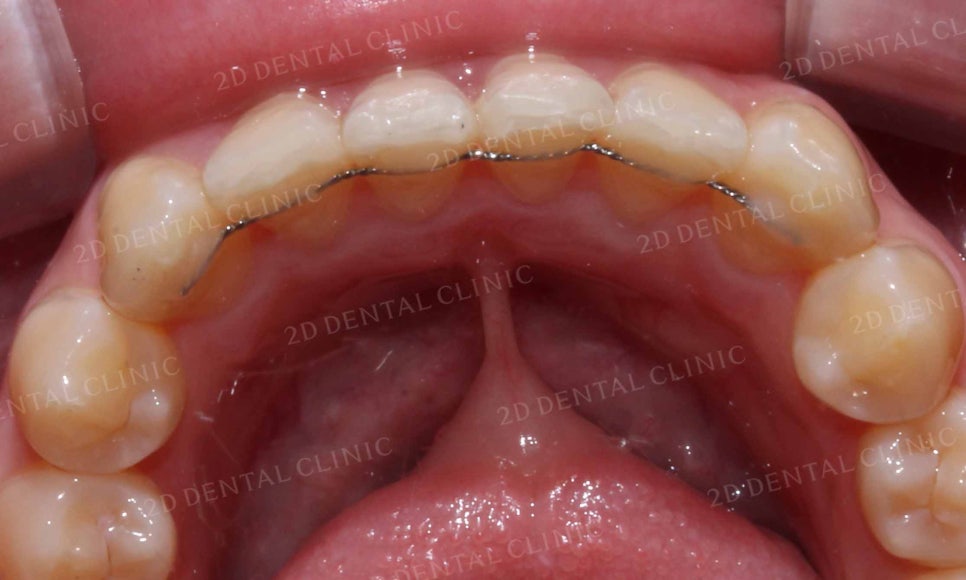

앞니의 뻐드러짐이 잘 나타나던 윗니 또한

토끼 앞니 교정 후 틀어졌던 치열이 가지런하게 바뀌고

밖으로 뻗어있던 앞니도 정상적인 각도로 교정된 모습이네요~

<Before> <After>

삐뚤삐뚤한 치열이었던 아랫니 역시

토끼앞니 교정 후 치열의 총생이 사라지고

완만한 곡선의 형태로 교정된 모습입니다.

이번 환자분께서는

토끼앞니 증상을 교정하기 위해

약 7개월의 교정 기간이 소요되셨으며

교정기간 중 심미성을 고려하여

2D교정방식을 선택하셨습니다.

2D교정의 경우 교정장치가

겉으로 드러나지 않아 심미성이

우수하다는 장점이 있지만

일반적인 교정법보다 치아에 고정력이

비교적 약하게 주어지기 때문에

교정기간이 예상보다 오래 소요될 수 있습니다.